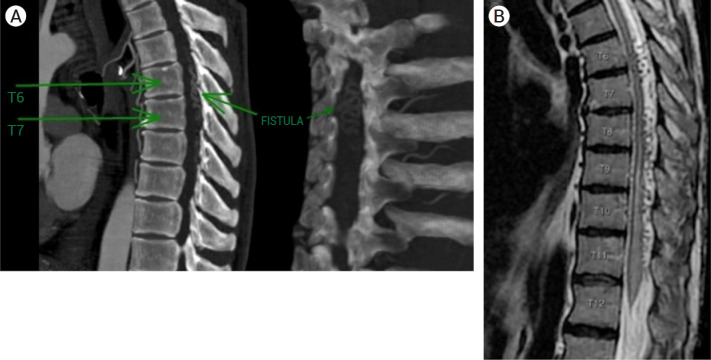

Foix-Alajouanine syndrome is an extremely rare yet important differential diagnosis for subacute lower limb weakness in middle-aged to elderly adults. Current understanding of the pathophysiology of this disease, along with recent publications on successful endovascular interventions, has shifted the perspective and clinical approach for its management. Nonetheless, neurosurgical pathways for clinical treatment are still preferred over endovascular embolization. Here, we present the case of a 63-year-old male who developed a rapidly progressing thoracic medullary syndrome over a 6-month period, compromising motor function, sphincter control, and sensory function in the lower extremities. The patient was diagnosed with venous congestive myelopathy secondary to a dural arteriovenous fistula and underwent endovascular embolization using hyper-selective catheterization. Over an 8-month period, the patient experienced successful recovery of both motor and sensory functions. This case supports the use of minimally invasive techniques for the treatment of dural arteriovenous fistulae with spinal involvement.